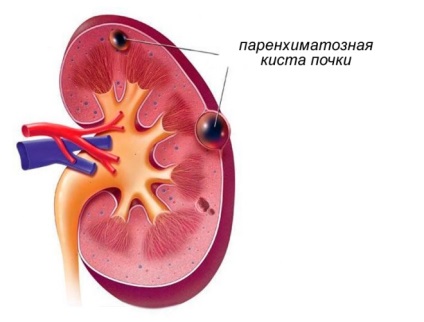

Cu varsta, rinichii pierde anumite tesuturi sanatoase devin mai slabe și mai rău decât lichidul filtrat, ușor supuse unor inflamații și boli infecțioase. Slăbit la rinichi și încep să se formeze chisturi parenchimului rinichi dreapta sau partea stanga a corpului. Chisturile sunt săculeți mici sau capsule de tesuturi moi, care umplu cavitatea sau cavitățile pe rinichi deteriorate și sunt formate, prin atașarea sau canale de flagele la părțile sănătoase ale organismelor.

persoanele mature și în vârstă sunt cele mai sensibile la chist intraparenchimala a rinichiului drept. pentru că rinichii de la această vârstă sunt mult mai probabil să slăbească, ca urmare a inflamației, bolilor și rănirilor transferate. Medicii cred că un procent mai mare de acest tip de chisturi provocate de boli genetice, care apar chiar și în placentă și să se îndrepte într-o formă ascunsă pe tot parcursul vieții. chist intraparenchimala al rinichiului stâng poate fi, de asemenea genetice în origine și apar la persoanele cu predispoziție la acest tip de tumori benigne.